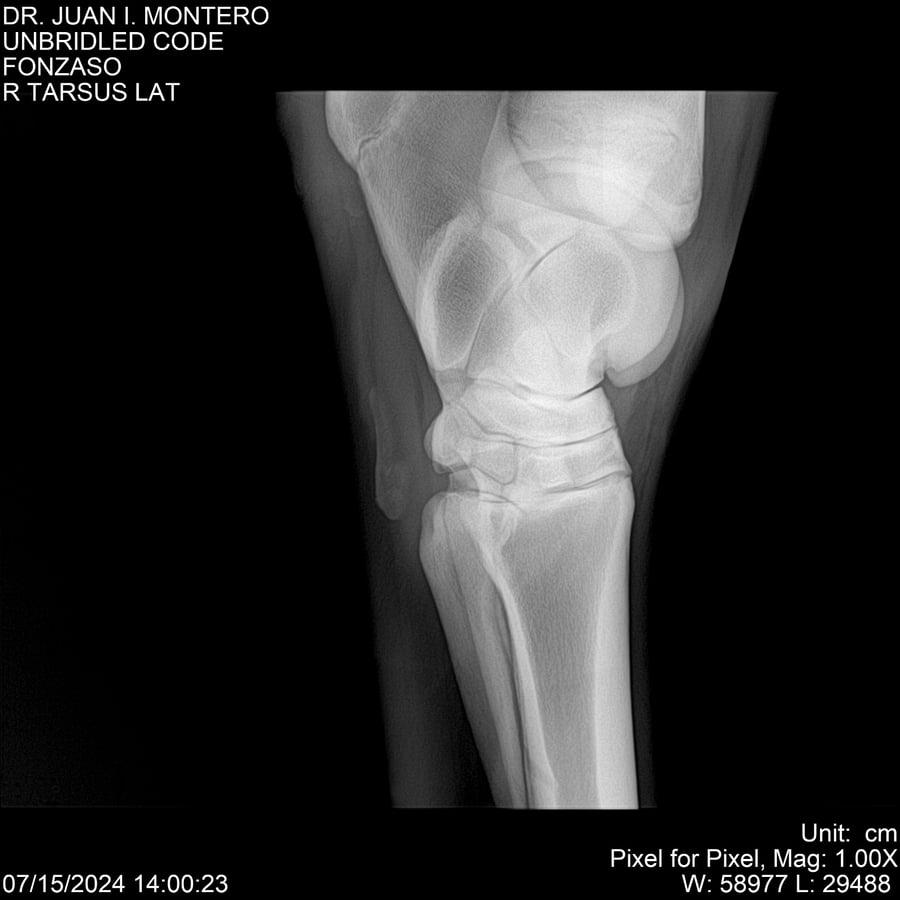

• Empresa: Abelenda N. R., Walter Hugo